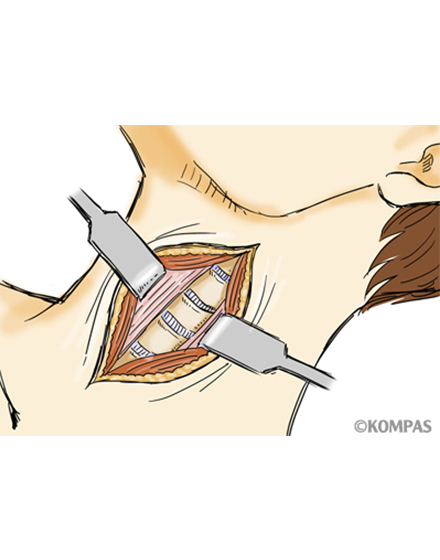

頚椎前方除圧固定術

適応となる疾患:頚椎椎間板ヘルニア、頚椎症性神経根症など

頚部の前方より切開し椎間板や骨の出っ張りを切除し、神経の圧迫を解除します。最近は、椎間板や骨を切除した部分に、椎体間ケージと呼ばれる箱型の金属を使用することで、腰骨からの採骨が不要となり手術時間が短縮できます。また、術後の採骨部痛(骨をとる部分の痛み)を防ぐことができます。手術時間は1時間~1時間30分ぐらいで、翌日から歩行が許可されます。入院期間は通常10~14日間ぐらいになります。